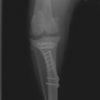

術前側面像

術前正面像

術前に25°であったTPAは、TPLO実施により7°に矯正されました。症例の歩行状態は良好です。